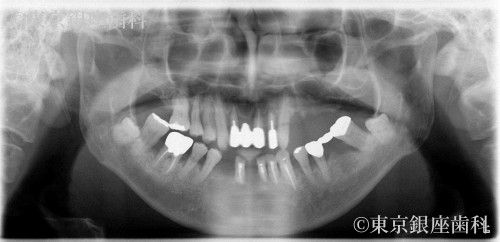

2型糖尿病の治療を経て歯周病の進行によって失われた咬合機能をワンデイインプラントにより回復。ただし費用の都合により上顎のみ手術。患者の希望により残存歯の多い下顎は義歯を使用した例。

Before

特に上顎の歯周病が進行していて歯の動揺、歯肉の腫れ、出血、咬合痛あり。歯石が帯状に付着しており磨き残しも多い。

手術に際し対診をとると2型糖尿病が発覚。糖尿病の治療で安定した全身状態にて手術に臨んだ。

今回は上顎のみを希望。動揺の激しい残存歯を抜歯、即時にインプラント4本の埋入と仮歯の固定で審美面の回復も行った。

下顎の動揺歯抜歯後の欠損部には作成した義歯を使用。